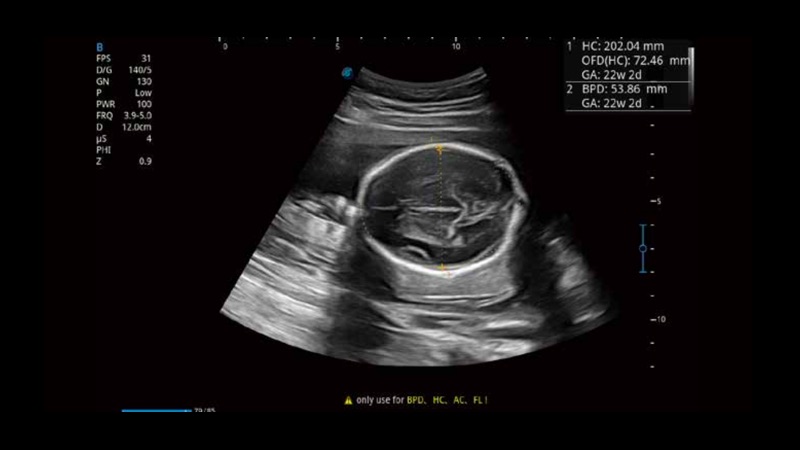

S-Fetus基于大數(shù)據(jù)深度學(xué)習(xí)算法,能夠幫助您在產(chǎn)前篩查過程中智能識別胎兒標(biāo)準(zhǔn)切面、自動測量并錄入報告。一個按鍵,即可智能、精準(zhǔn)、高效地獲取胎兒生理指標(biāo),極大簡化您的產(chǎn)科檢查操作。

可快速對產(chǎn)科掃查切面完成胎兒生理學(xué)參數(shù)的自動測量,減少操作者按鍵次數(shù),大幅提升檢查效率。

自動識別頸項透明層并獲得NT值,為早孕胎兒畸形篩查提供有效測量工具,提高診斷效率和診斷信心。